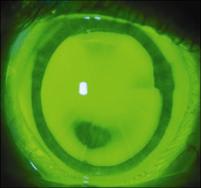

The patient is pleased with the lens performance, but he has developed 360 degrees of peripheral neovascularization at the incision sites (Figure 3). We continue to monitor the vascularization every four months and encourage as minimal wearing time as possible.

Figure 3. Incisional neovascularization with SynergEyes lens wear.